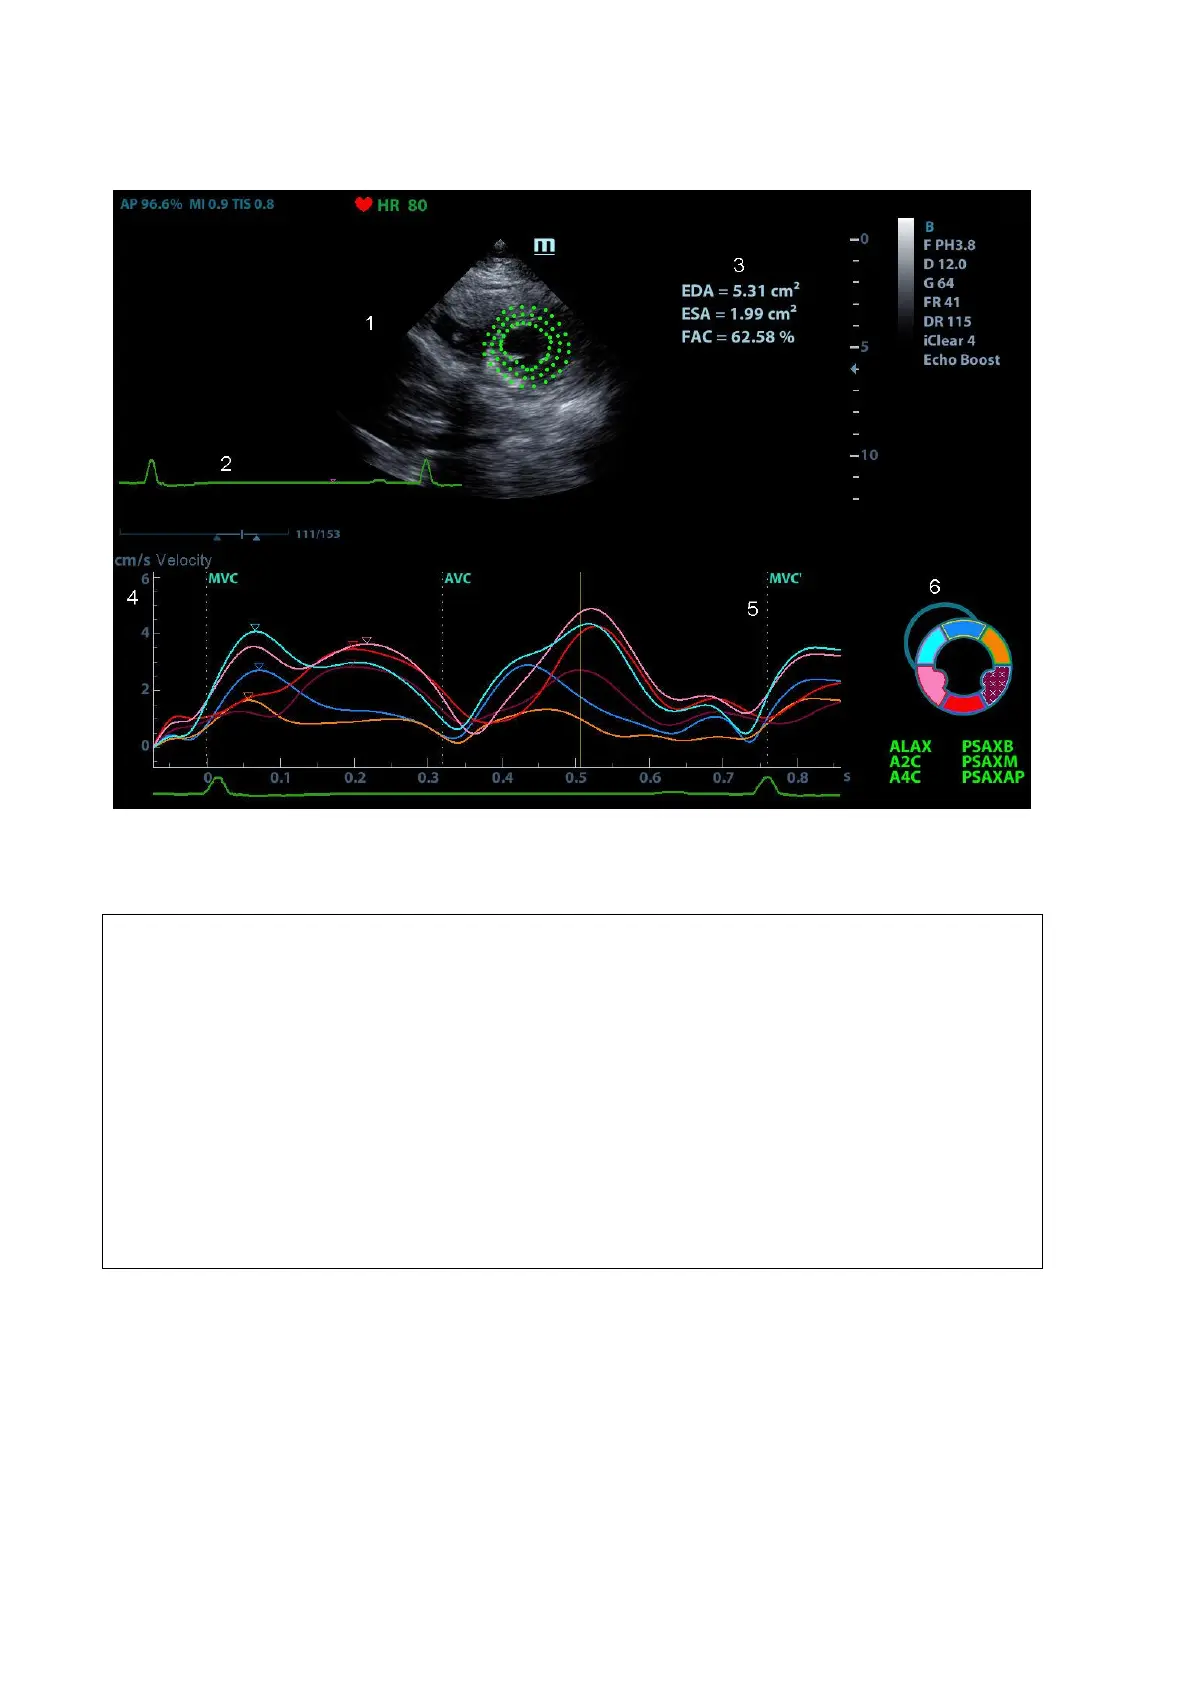

5.15.2 Tissue Tracking QA Screen Description

1Displays image used to generate trace curve

2Displays ECG trace

3Displays measurement and calculation results:

EDV:

maximum value of the end diastolic volume during the trace.

EDA:

maximum value of the end diastolic area (Left Ventricular) during the trace.

ESV:

maximum value of the end systolic volume (Left Ventricular) during the trace.

ESA:

maximum value of the end systolic area (Left Ventricular) during the trace.

FAC:

Fractional Area Change= (EDA ESA)/EDA.

This parameter is available under short axis section.

EF:

Ejection fraction.

This parameter is available under long axis section.

HR:

Heart rate.

GS:

Global Strain